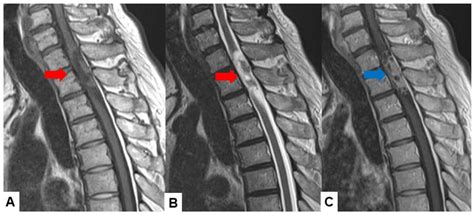

A cancer tumor back diagnosis generally refers to an abnormal growth of cells located within the spinal canal or the bones of the spine (vertebrae). These tumors are classified based on their location: intradural-extramedullary (inside the spinal canal but outside the spinal cord), intramedullary (inside the spinal cord), or extradural (outside the spinal cord, often involving the bone).

MRI Scan The gold standard for visualizing soft tissues and nerve compression.